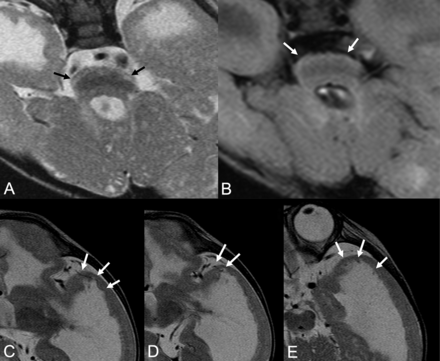

Brain stem (A and B) and left temporal (C–E) MRIs of patient 20. A brain stem T2WI (A) shows a fluffy structure and high intensity of the hypoplastic pontine surface (black arrows). The FLAIR image (B) detects high intensity of the pontine surface (white arrows). Left temporal T2WIs (C–E) show lissencephaly, which contains abnormally located superficial cortical vessels running through and beneath the cortex (white arrows).

Abnormally located superficial vessels beneath the cortex were observed in 3 patients (11.1%). The vessels ran through, inside, or beneath the lissencephalic cortex, and they were recognizable especially in the temporal lobes (Figs 1D–F and 2C–E). Hypoplasia of superficial cerebral veins around the frontal lobes was noted in all 5 patients who had SWI findings (Figs 1I and 3C, -D). Dilated and tortuous subependymal veins were identified in 2 of these 5 patients (40.0%) on SWI (Figs 1I and 3C, -D).